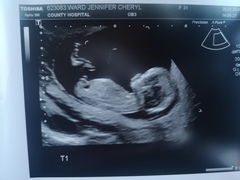

Had my scan yesterday putting me slightly more ahead at 13+3. Both babies lovely and wriggly, neither really wanting selfies as kept turning away. Twin 2 was very chilled out just hanging around with legs stretched and crossed and arms behind head lol. Starting to feel so more real again. Having another phase of oh shit, there's two humans inside of me! 🤯

@Sunflower1608 that's brilliant news and those are gorgeous clear scan pictures! Measuring ahead with twins is great. Pleased you've had a nice positive scan